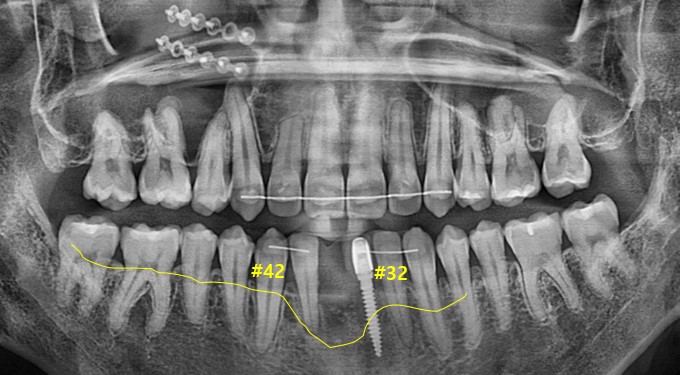

▲초진 구강 사진 ▲초진 파노라마사진

#41 치아는 임플란트를 하시고 위에 말씀드린 것처럼 골 유착 실패로 제거 후 내원해 주셨습니다.

#31번 치아는 임플란트 치아였으나 예후가 좋지 않아 제거 후

#41 31 임플란트를 심을 치료 계획을 가졌으나

노란 선을 보시면 잇몸이 다른 부분들에 비해 심하게 꺼져 있다는 것을 확인할 수 있는데요

기본적으로 잇몸살과 뼈가 제일 약한 부위가 앞니이기 때문에 쉽게 잇몸이 내려앉을 수도 있습니다.